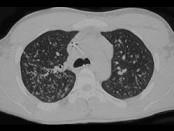

问题 男,26岁,发热,夜间盗汗,咳嗽半月余,请结合CT检查选出最可能的诊断 ( )

选项 A.粟粒型肺结核 B.间质性肺炎 C.弥漫型肺癌 D.肺转移瘤 E.硅沉着病

答案 A